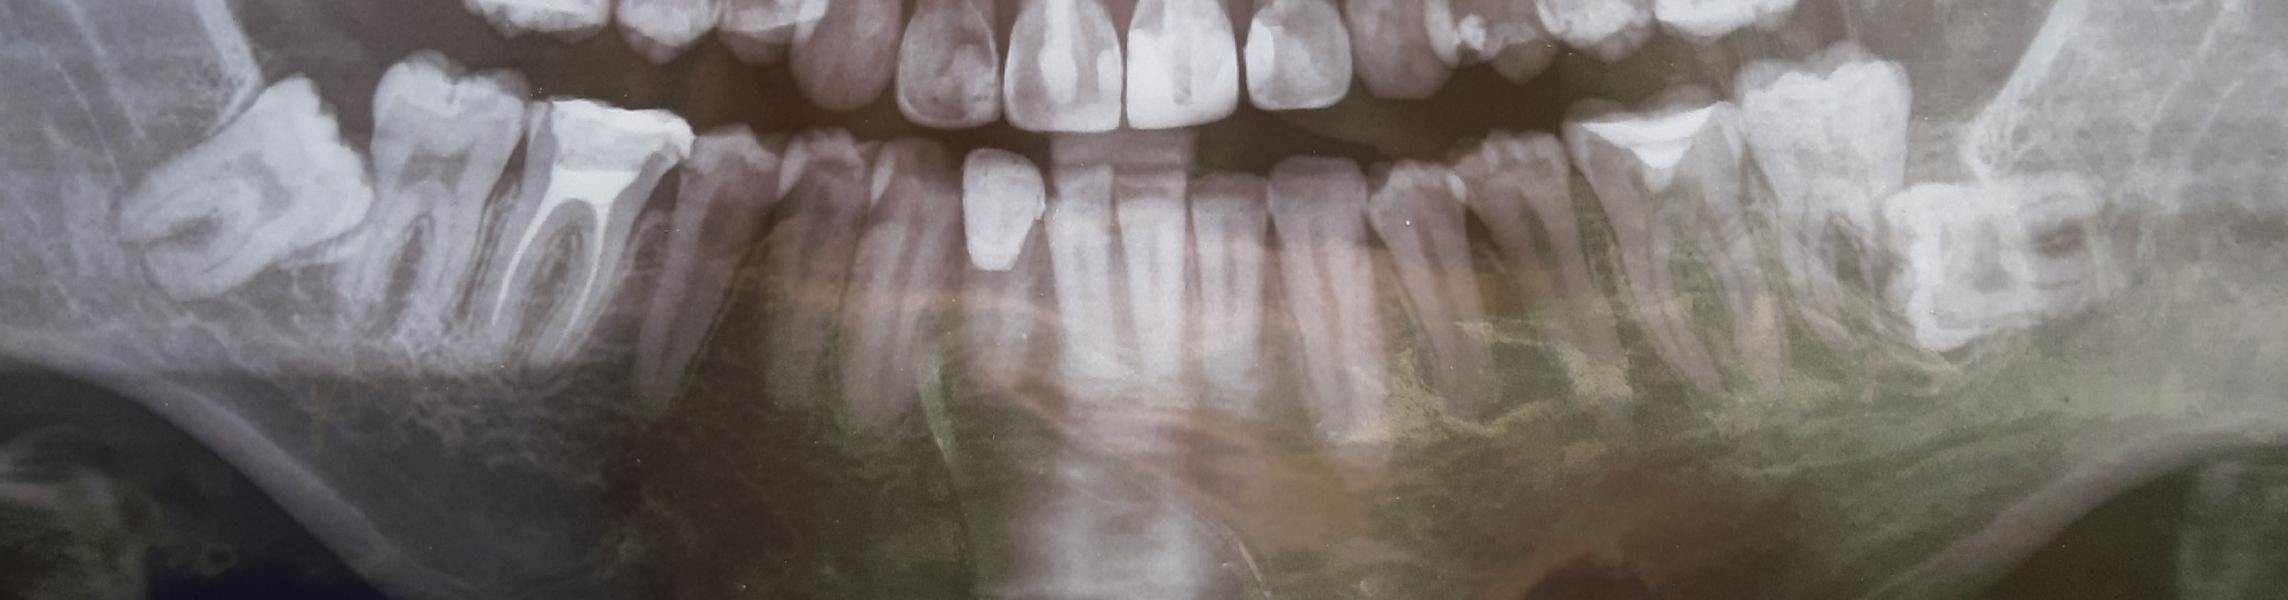

Делала сегодня панорамный снимок зубов. Зуб мудрости растет горизонтально🤯 . Удалять его 100% надо? Я думаю и тот,что под углом скажут удалить. Кто сталкивался? Что делали?

Те, что не вылезли и не двигают вам зубной ряд можно не удалять. У меня пол углом лежал, как у вас слева на снимке - надо было. Он немного уже торчал и от этого портился бы со временем сам и соседний зуб. Моей подруге удаляли такой, как у вас справа, был под десной, но уже съехали передние зубы один на другой, теперь придется брекеты ставить. Выберите хорошего хирурга и эти зубы рвать по 10 мин, у меня ровно столько заняло на каждый. Вообще нечего переживать)))

Удалить надо 💯, и как можно скорее, у вас на снимке зубы мудрости упираются и портят корни седьмых зубов

Удаляйте. Из-за неправильного расположения, эти зубы постепенно будут двигать остальные зубы. А, поскольку, место ограничено, зубы что внутри, будут съезжаться, разворачиваться, меняться прикус может.

Лучше советуйтесь с вашим стоматологом, сделайте кт нижней челюсти, чтоб посмотреть в 3д изображении расположение 8-х зубов по отношению к 7-у зубу